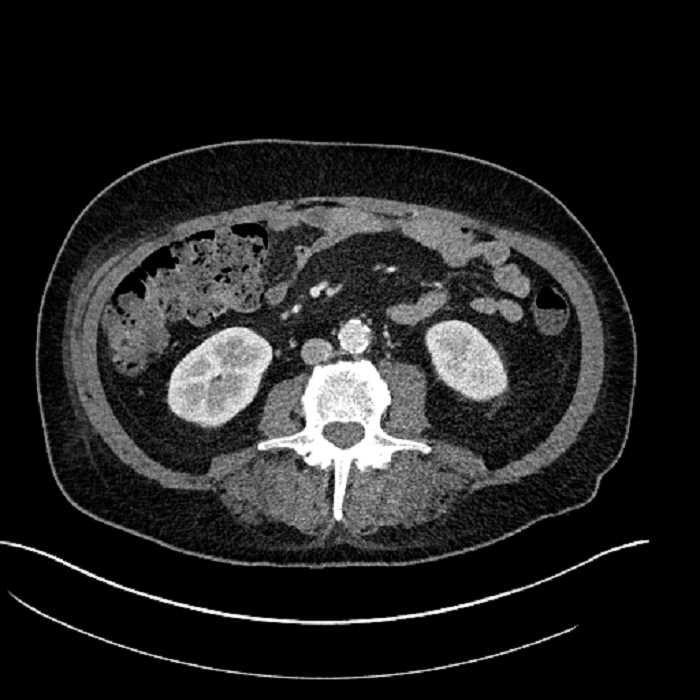

Age: 63

Sex: Male

Indication: Abdominal pain

• Large fluid density structure in hepatic segments 7 and 8 measuring 10 x 7 x 7 cm with internal septation and circumferential ill-defined low density compatible with edema

• Peripherally enhancing subcapsular collections along the anterior margin of the left hepatic lobe measuring 3 x 1 cm and 2 x 1 cm

• Clearly marginated fluid density structure in segment 7 and several other scattered tiny hypodensities, which likely represent cysts

• Hepatic abscess

Acute sigmoid diverticulitis complicated by a small contained perforation and a large abscess in the right hepatic lobe. Additional small subcapsular abscesses along the anterior margin of the left hepatic lobe.

• The classic CT imaging appearance is a double target sign with internal low density surrounded by an internal enhancing rim (capsule) and a low density external rim (edema)

Hepatic abscess showing the double target sign with low density internally surrounded by a thin inner enhancing rim (red arrow) and ill-defined outer low density rim (yellow arrow). Blue arrow indicates an internal septation. Red arrows: additional smaller subcapsular abscesses. Red arrow: focal contained perforation associated with diverticulitis.